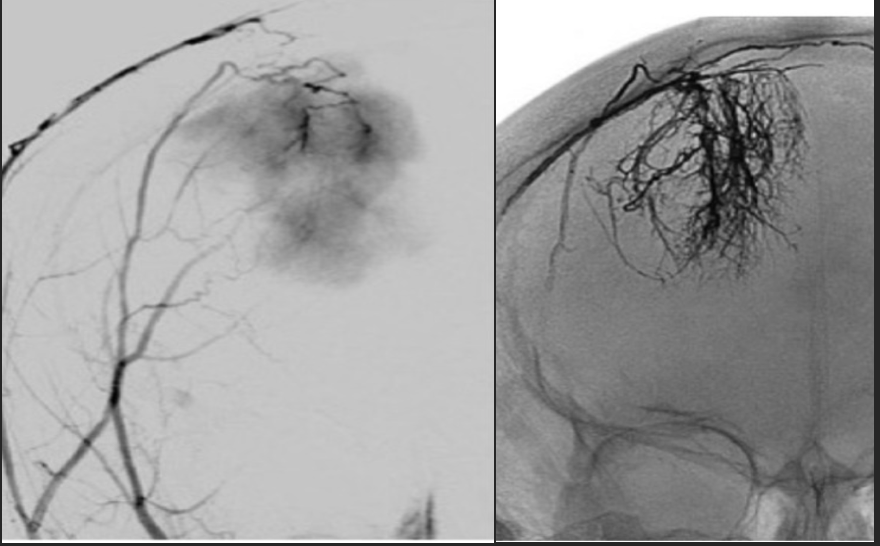

A embolização pré-operatória de meningioma (EPO) intracraniano é realizada em todo o mundo. Embora evidências claras da eficácia da (EPO) não tenham sido relatadas na literatura, a técnica desempenha um papel importante na cirurgia aberta, especialmente para meningiomas grandes ou da base do crânio.

Os objetivos da embolização incluem:

- indução de necrose tumoral, resultando em uma operação mais segura

- redução do sangramento intraoperatório

- diminuição do tempo operatório.